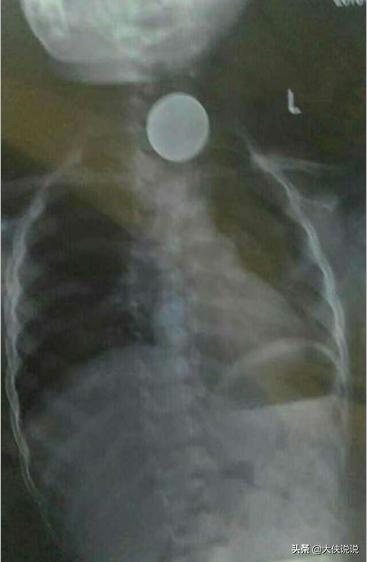

这个是国外的一个异物取出的视频,国内也有类似的操作记录,但是毕竟是少数,看着很简单,还是有风险的。

今天也遇到一个类似的病人,可惜,没人愿意尝试这样的方法,最后在全麻下纤支镜也顺利的取出了,